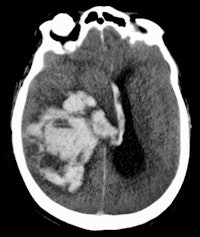

Postmortem imaging is performed at Erasmus University Medical Center.The primary outcome measure was performance of minimally invasive autopsy and conventional autopsy in establishing immediate cause of death, as compared with consensus immediate cause of death. The group also compared the diagnostic yield of the minimally invasive technique with conventional autopsy for all, major, and grouped major diagnoses; frequency of clinically unsuspected findings; and percentage of answered clinical questions.

The two methods showed comparable performance in determining immediate cause of death, with agreement in 91 of 99 (92%) of cases. Minimally invasive autopsy found the consensus cause of death in 96 of 99 cases, with the technique missing one case of myocardial infarction, one case of ischemic colitis, and one case of bowel ischemia, whereas conventional autopsy found the consensus cause of death in 94 of 99 cases, misdiagnosing five cases. There was no statistically significant difference between the rates.

The minimally invasive technique made a higher total number of diagnoses than traditional autopsy, establishing 259 (90%) grouped major diagnoses related to consensus cause of death, compared with 224 (78%) of 288 for conventional autopsy.

Dr. Wolter Oosterhuis, PhD, from Rotterdam.The advantages of the minimally invasive method included perfect depiction of pathologies such as pneumonia, sometimes overlooked in traditional autopsy due to the thickness of organ slices. In addition, MRI appeared highly sensitive for guiding tissue sampling in the diagnosis of acute myocardial infarction. However, the minimally invasive approach had trouble identifying bowel ischemia, because it is difficult to spot early necrosis in the bowel wall or obtain samples when it can be seen.